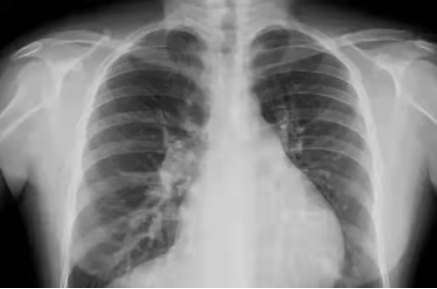

X線檢查

原理簡介:人體內(nèi)部組織的密度不同,所以射線穿過身體時有些地方能穿透,有些地方不能穿透。比如肺被穿透后,在X線片上就是黒的,因為它沒有阻擋,膠片能夠全部曝光,所以呈現(xiàn)出來是黑的。而骨骼不容易穿透,顯示出來就是白的。

應(yīng)用:主要看密度,擅長骨折、肺臟病變等

優(yōu)點:作用廣、快捷、檢查費用低;

缺點:受制于深淺組織的影像相互重疊和隱藏,有時需要多次多角度拍片才能看清楚;

影像舉例

胸片能夠顯現(xiàn)我們的肺、心臟、縱膈、氣管,這么多器官都在一張片子上,所有器官的影像前后壓縮,變成了一張平片。所以,X線片是很多器官重疊在一起。

但是,如果肺部顯示有陰影,是肺結(jié)核?肺炎?還是腫瘤?X線是不能辨別的。